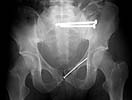

On admission patient was hypotensive. Evaluation revealed him to be having an unstable pelvic ring injury, D12 vertebral body fracture, free fluid in the abdomen and a suspected urinary bladder injury. After his haemodynamic status was better he was taken up for an emergency laparotomy (midline approach). Though there was free blood stained fluid in the peritoneum no hollow viscus injury or other organ damage was noted. Urinary bladder contusion present but no tear. At he same sitting the anterior pelvic ring was stabilised using reconstruction plates through an extended Pfannensteil approach. After a couple of days the posterior ring was stabilised using reconstruction plates (posterior approach). The spine was not interfered surgically since this was inherently stable and there were no neurological findings. The posterior wound grumbled for some time and settled down. He was kept in bed but allowed free turning in bed.

The X rays and few CT reconstructions attached. Kindly give your valuable comments. What all would have been better ways of management?